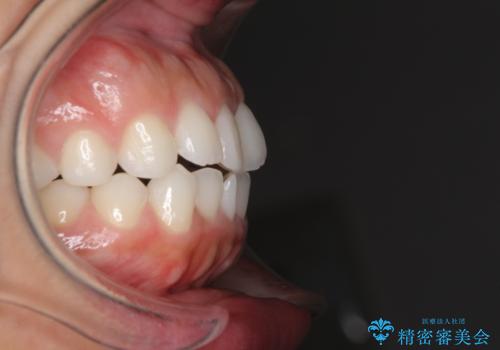

目立たない装置で横顔のシルエットを改善 ハーフリンガルでの抜歯矯正

- 矯正装置

- ハーフリンガル

- 口元の突出感を気にして来院された患者様です。

上下左右の第一小臼歯4本を抜歯して口元を下げる治療計画としました。